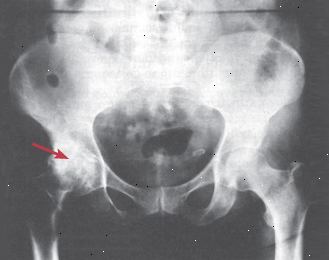

Ακτίνες-Χ. Περισσότερες μορφές αρθρίτιδας μπορεί να προκαλέσει κοινές ανωμαλίες ορατό σε ακτίνες Χ (βλέπε σχήμα 4). Αλλά στις περισσότερες περιπτώσεις, οι αλλαγές αυτές δεν μπορούν να ανιχνευθούν μέχρι μήνες μετά την εκδήλωση της νόσου. Μερικές φορές οι αλλαγές είναι αρκετά ειδικές και προτείνουν ένα συγκεκριμένο είδος της αρθρίτιδας. Σε άλλες περιπτώσεις, είναι πιο γενικά. Για παράδειγμα, βλάβη των οστών (που ονομάζεται διάβρωση) βρίσκεται συχνά σε ασθενείς με ρευματοειδή αρθρίτιδα και μπορεί να συμβεί σε ουρική αρθρίτιδα, αλλά η ζημιά από κάθε αιτία διαφέρει αρκετά σε εμφάνιση ότι ένας ακτινολόγος μπορεί να τους πει συνήθως χώρια.

Σχήμα 4: οστεοαρθρίτιδα του ισχίου Αυτό το x-ray, ή ακτινογραφία, δείχνει οστεοαρθριτικό αλλαγές στο αριστερό ισχίο. Το κανονικό του σχήμα "ball-in-υποδοχή" έχει επιδεινωθεί αισθητά. |